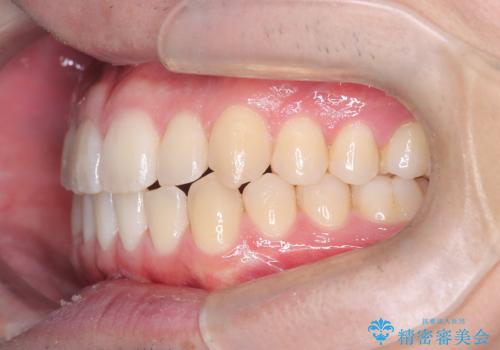

- 八重歯が気になるとのことでご来院されました。お口の中を確認すると、上の前歯がスペース不足で押し出され、少し前に出ている状態でした。抜歯せずに整えるため、奥歯を少しずつ後ろに動かしながら(遠心移動)、歯と歯の間をわずかに削るIPRを行ってスペースを作ることにしました。また、上下の噛み合わせを整えるために2級ゴム(エラスティック)を使用する方針を立てました。

マウスピースを段階的に交換しながら、奥歯を少しずつ後ろへ動かし、八重歯がきれいに並ぶよう調整しました。前歯の突出感を抑えるためにIPRを行い、スムーズに配列。さらに、2級ゴムを活用して噛み合わせも改善しました。治療後は、自然な歯並びになり、笑顔に自信が持てるようになったと喜んでいただきました。